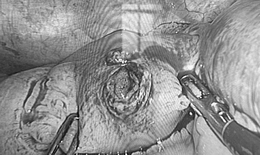

Việt kiều Mỹ 73 tuổi lựa chọn về Việt Nam phẫu thuật khối u đại tràng ác tính

Camera bệnh viện - 10/10/2025 14:55SKĐS - Việt kiều Mỹ 73 tuổi quyết định đến Bệnh viện Đa khoa Thủ Đức để thăm khám sau khi xuất hiện các dấu hiệu bất thường về đường tiêu hóa. Kết quả phát hiện khối u đại tràng ác nên nhanh chóng được phẫu thuật cắt bỏ.